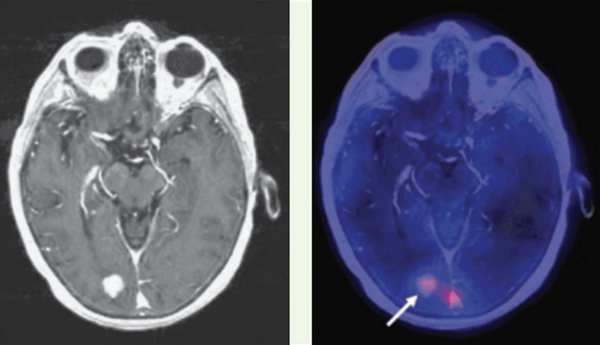

Позитронно-эмиссионная томография (ПЭТ) в диагностике вторичных опухолей ЦНС

Типичная картина вторичных очагов в головной мозг при ПЭТ — наличие зон повышенного захвата радиофармпрепарата (ФДГ — фтордезоксиглюкоза, либо препаратов меченых аминокислот, таких как метионин) с наличием очагов некроза, протяженных зон отека со сниженным захватом ФДГ.

![метастазы в мозг ПЭТ]()

Как выглядят метастазы на ПЭТ-КТ? Здесь виден опухолевый очаг в правой затылочной доле, значительно накапливающий РФП (меченный радиоактивным фтором метионин). ПЭТ-КТ — метод, признанный «золотым стандартом» не только в выявлении метастазов в мозг, но и позволяющий достоверно отличить их от других образований (кисты, абсцессы, гематомы, каверномы и т.п.). От тщательного анализа ПЭТ зависит результат диагностики.